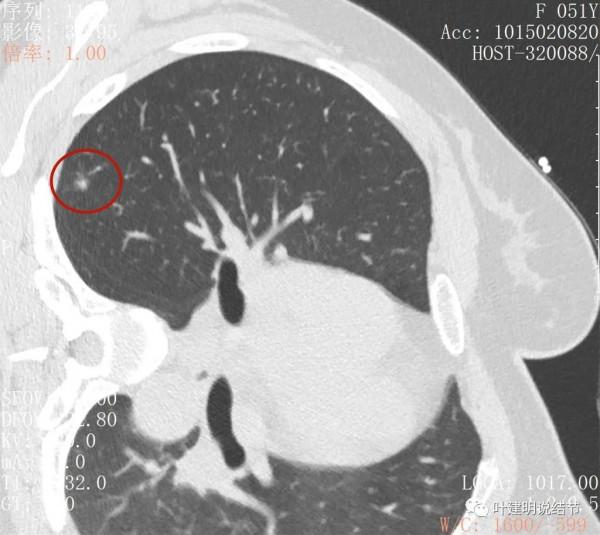

金華的某A,是我同學的大姨子,前段日子因為同學的愛人查出肺結節是早期肺癌,所以她姐姐記起來2年前也查出有肺結節,但沒有複查過,怕也得肺癌,所以到我門診來複查。我們先來看她平掃的CT影象:

右肺上葉後段磨玻璃結節

感覺是混合磨玻璃,而且密度偏高

見邊緣不光整,似有細毛刺

整體輪廓清楚

有微血管徵

胸腔有輕微牽拉

從平掃看,病灶雖然小,但就不舒服,極可能是惡性的。我們再來看她其餘部位還有小結節: